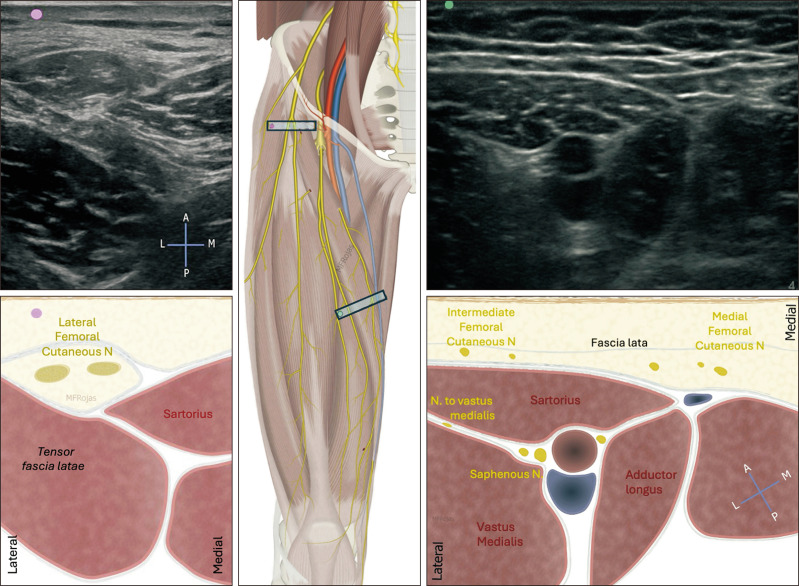

Genicular nerve radiofrequency ablation: proposal of a technical protocol for managing procedural pain.

膝神经射频消融术:处理程序性疼痛的技术方案建议。